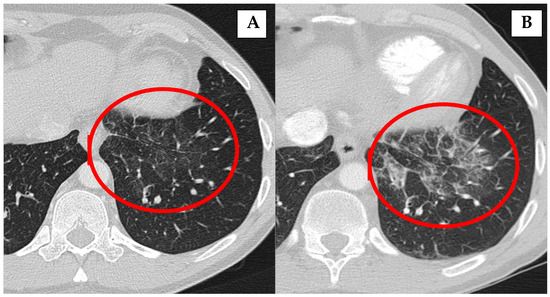

| 1 | female | 53 | Type 1 | 1 year after AIP diagnosis: “ground-glass” appearance; relapse after 12 years of AIP diagnosis with pleura thickening and mediastinal lymph nodes enlargement | No treatment | Former (13 PY) |

| 3 * | male | 66 | Type 1 | 9 months after AIP diagnosis: nodular lesions in lungs | Rituximab and CST 2.5 mg | Never |

| 4 * | female | 65 | Type 1 | 2 months after AIP diagnosis: nodular lesions in lungs | Rituximab | Never |

| 5 * | male | 85 | Type 1 | At the time of AIP diagnosis: non-specific infiltrates in both lung lobes | Previously treated with CST, currently no treatment | Former (10 PY) |

| 6 * | female | 24 | Type 1 | At the time of AIP diagnosis: infiltrates in both lung lobes with pleural effusion | Previously treated with CST, currently no treatment | Never |

| 8 | female | 73 | Type 1 | 5 months after AIP diagnosis: nodular lesions in lungs | Previously treated with CST, currently no treatment | Never |

| 10 | female | 60 | Type 1 | 3 years after AIP diagnosis: “ground-glass” appearance and pleura thickening | Previously treated with CST, currently no treatment | Former (10 PY) |

| 11 | male | 69 | Type 1 | 5 years after AIP diagnosis: nodular lesions in lungs | Previously treated with CST, currently no treatment | Never |